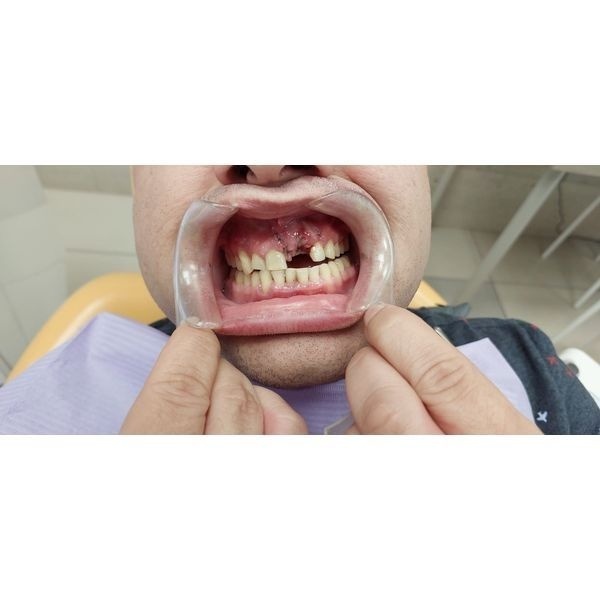

В «Центр лечения заболевания пародонта» обратился 40-летний мужчина, у которого выпал левый верхний резец (зуб 2.1).

Слизистая оболочка альвеолярных отростков обеих челюстей покрасневшая и отёчная, при зондировании кровоточила. Отмечались над- и поддесневой зубной камень тёмного цвета. Правый нижний клык и резец (зубы 1.3 и 4.1) шатались в обе стороны. Слизистая оболочка в области выпавшего зуба сформирована двумя слоями.

Глубина пародонтальных карманов — 7 мм. При прощупывании десны в области верхушек корней центральных зубов из них выделялось серозно-гнойное содержимое.